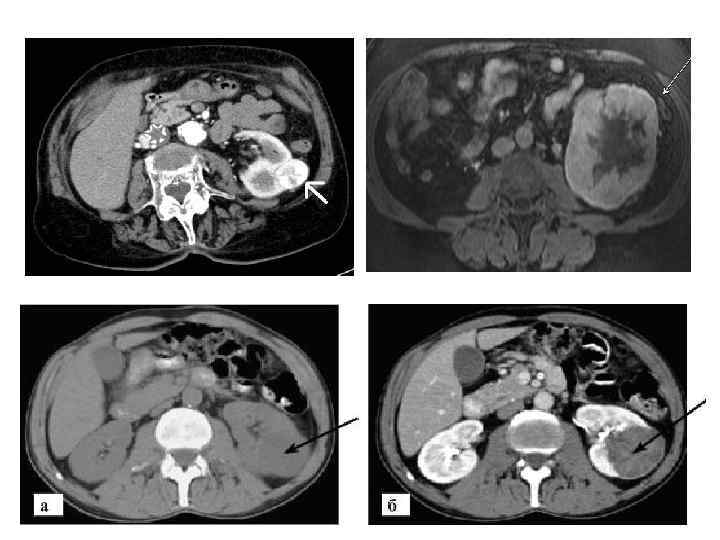

Диагностика рака почки. • Лабораторные исследования: ПАК, ПАМ, Б/Х крови, коагулограмма. • Лучевая диагностика: УЗИ ОБП, КТ, МРТ • Другие виды исследований: почечная артерио и каваграфия, динамическая нефросцинтиграфия.